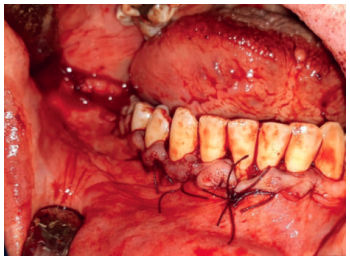

A nivel local, se anestesiaron los nervios alveolar inferior y bucal mediante articaina 40mg/ml con 0.01 mg/ml de epinefrina (Ultracain® , España). Se realizó una incisión intrasulcular a espesor total con una descarga distal alta en la rama mandibular que se extendió hasta distal del canino inferior izquierdo sin necesidad de realizar una descarga en este punto. Se despegó el colgajo con la ayuda de un periostotomo para poder acceder a la superficie ósea. Con pieza de mano y fresa redonda de carburo de tugsteno se realizaron tres cavidades equidistantes: la primera a la altura del trígono retromolar (Figura 5), la segunda apical a los premolares inferiores derechos y la tercera mesio-apical al canino inferior derecho. Dichos accesos permitieron abordar y despegar toda la lesión en su extensión para posteriormente poder traccionar de ella a través de la cavidad media (Figuras 6 y 7). La cavidad posterior sirvió también para realizar la exodoncia del cordal (Figura 8). Tras la eliminación del quiste se llevó a cabo un legrado minucioso de la cavidad remanente y se limpió con agua oxigenada. A continuación, se colocó la mini placa con una extensión desde la rama mandibular hasta mesial de la cavidad media. Por último, se reposicionó el colgajo y se suturó de forma hermética mediante una sutura poliamida recubierta no reabsorbible de 4/0 Supramid (Aragó® ) (Figura 9). La muestra obtenida se conservó en formaldehido al 10% y se envió al anatomopatólogo, el cual confirmó el diagnóstico de quiste dentígero sin displasia celular (Figuras 10 y 11).